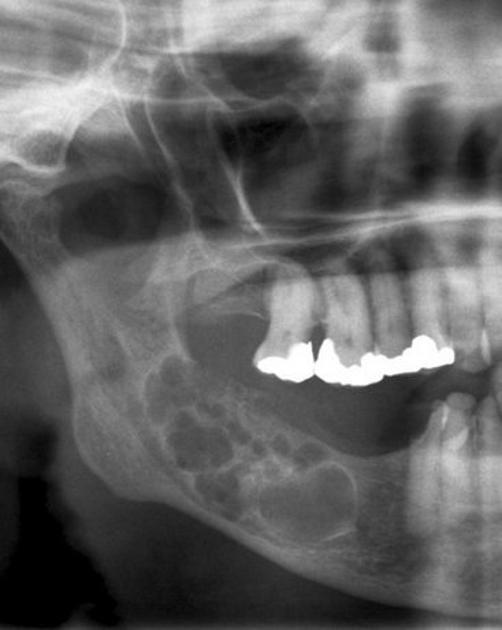

Ameloblastoma